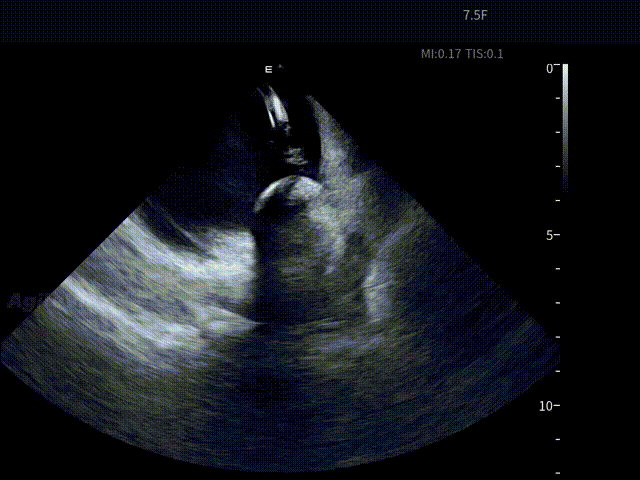

球囊充气

球囊复温后“Blood Bubble”